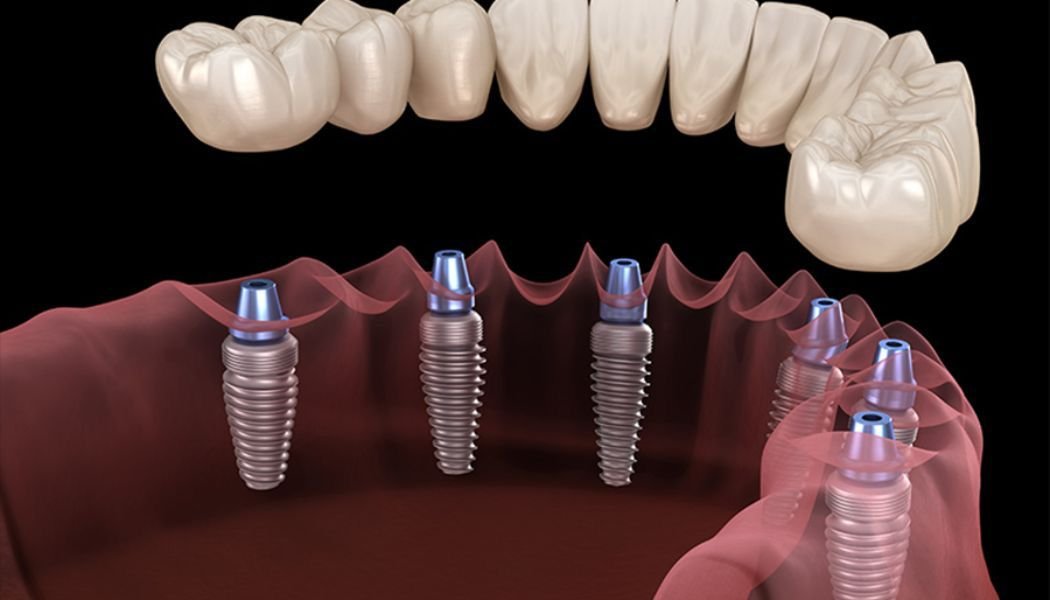

All-on-6 is an advanced implant technique where six dental implants are placed in the jawbone to support a fixed full arch of teeth (upper or lower jaw).

Compared to All-on-4, the additional implants provide:

• Greater load distribution

• Increased stability

• Enhanced long-term support